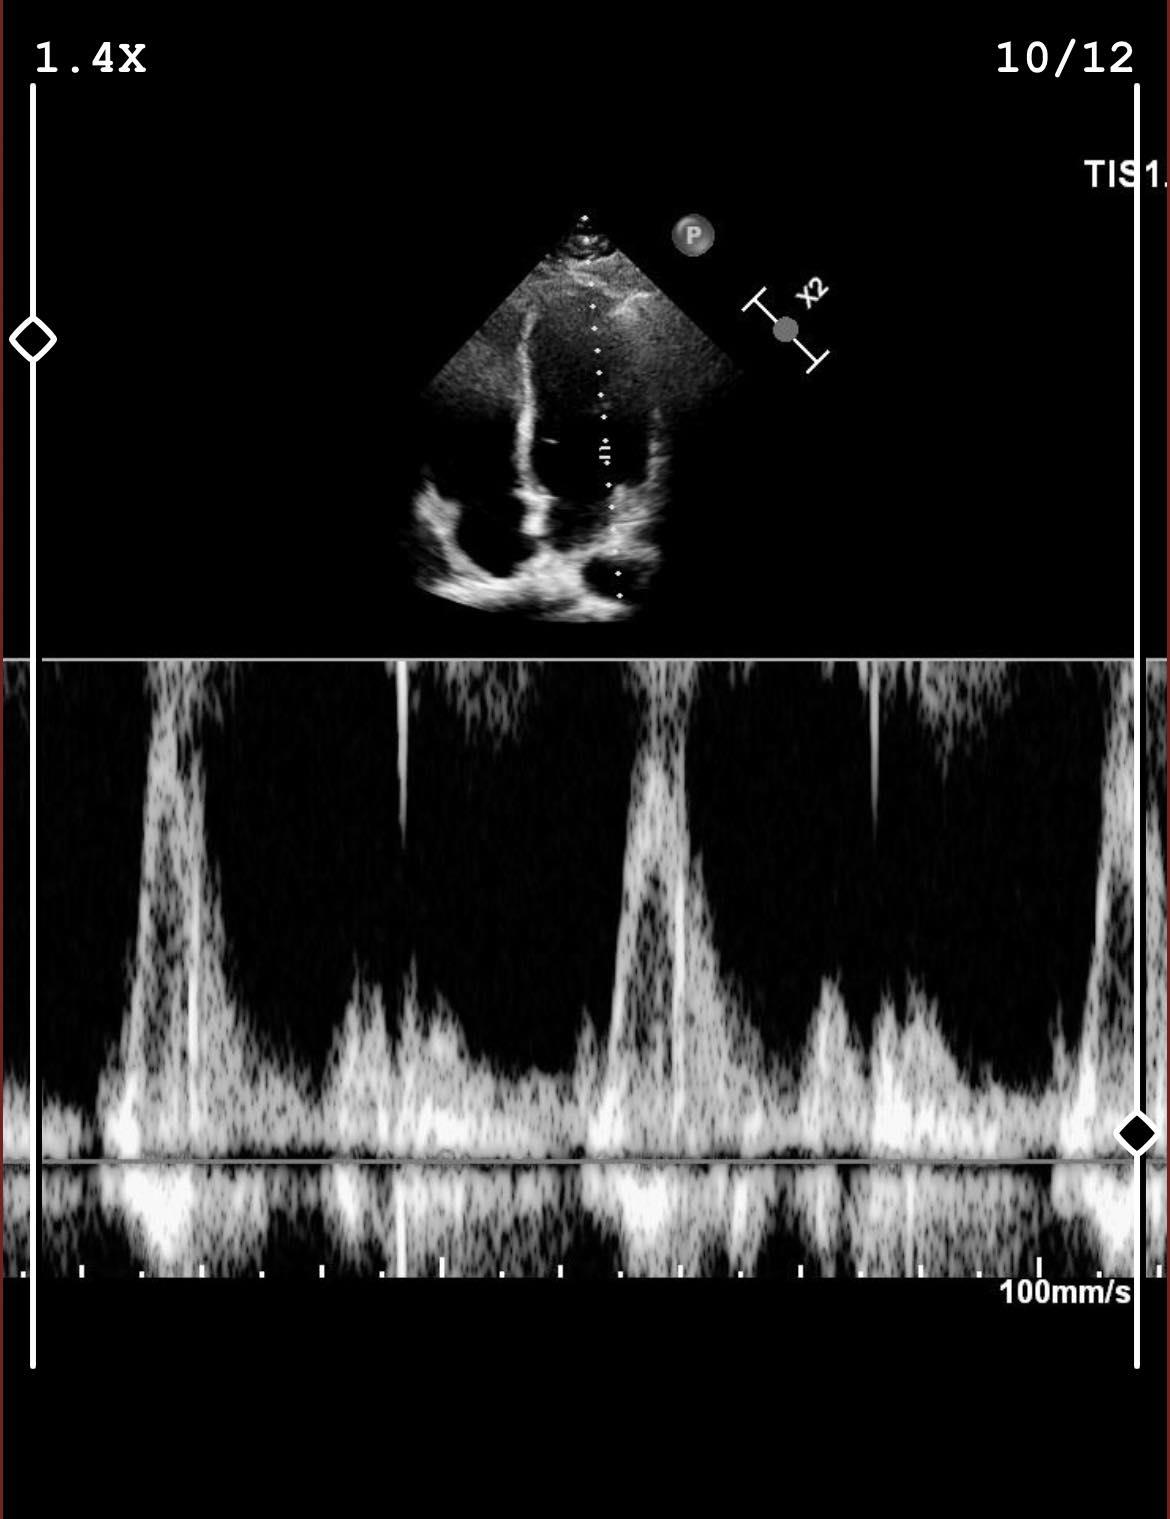

hastaneden gelen eko sonuçlarında sauronun mührünü görünce geçmiş rüyalarıma anlam katan olay. güç yüzüğünün yok edilmesi sonrası lotr evreninden sürgün edilen sauron'un ruhu 1936 senesi ağustos ayında ekin biçen dedeme girer(girer derken ruhen yani). dna kalıtımı yoluyla ailenin ilk erkek çocuğuna aktarılan sauron geni 2023 ağustosunda eyyam-ı bahur sıcaklarıyla yeterli gücü topladıktan sonra şahsımla beraber dünyayı yönetme planlarına başlamış bulunmaktadır. biraz finansal sıkıntılarımız mevcut, komutan kademesine bağış yoluyla alımlar yapılacaktır iletişim dm.

görsel